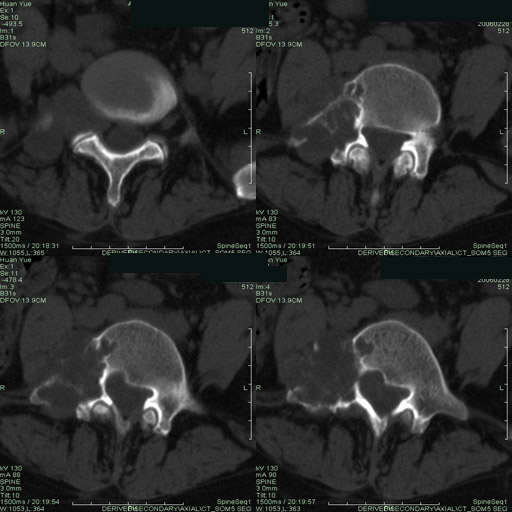

以下是引用听蝉观竹在2006-3-5 23:09:00的发言:[br]这个病例不考虑神经源性肿瘤,首先考虑转移瘤,因为它不是受压造成骨质吸收,而是从骨骼的松质部分由中心向外破坏的,不仅仅是横突,而且同侧椎弓根也破坏了。[br]神经源性肿瘤-----受压造成骨质吸收。[br]转移性肿瘤------从骨骼的松质部分由中心向外溶骨破坏,多见椎弓根也破坏。

以下是引用徐大夫在2006-3-5 20:32:00的发言:[br]骨缺损区边缘有硬化,结合部位,考虑神经源性良性肿瘤。